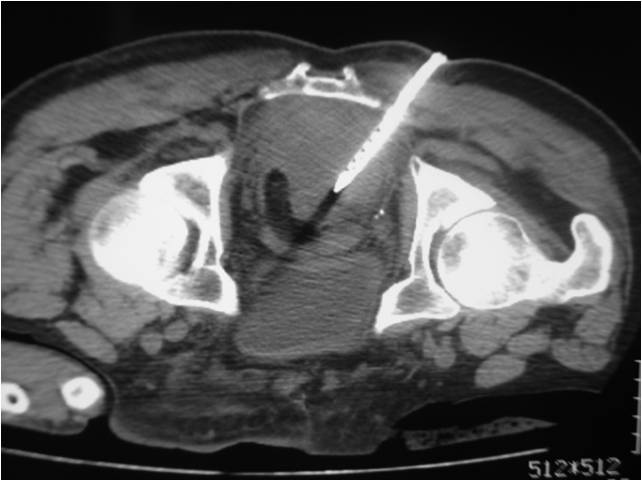

- Paracentisis of a deep pelvic abscess

- Successful catheter placement in a deep pelvic abscess